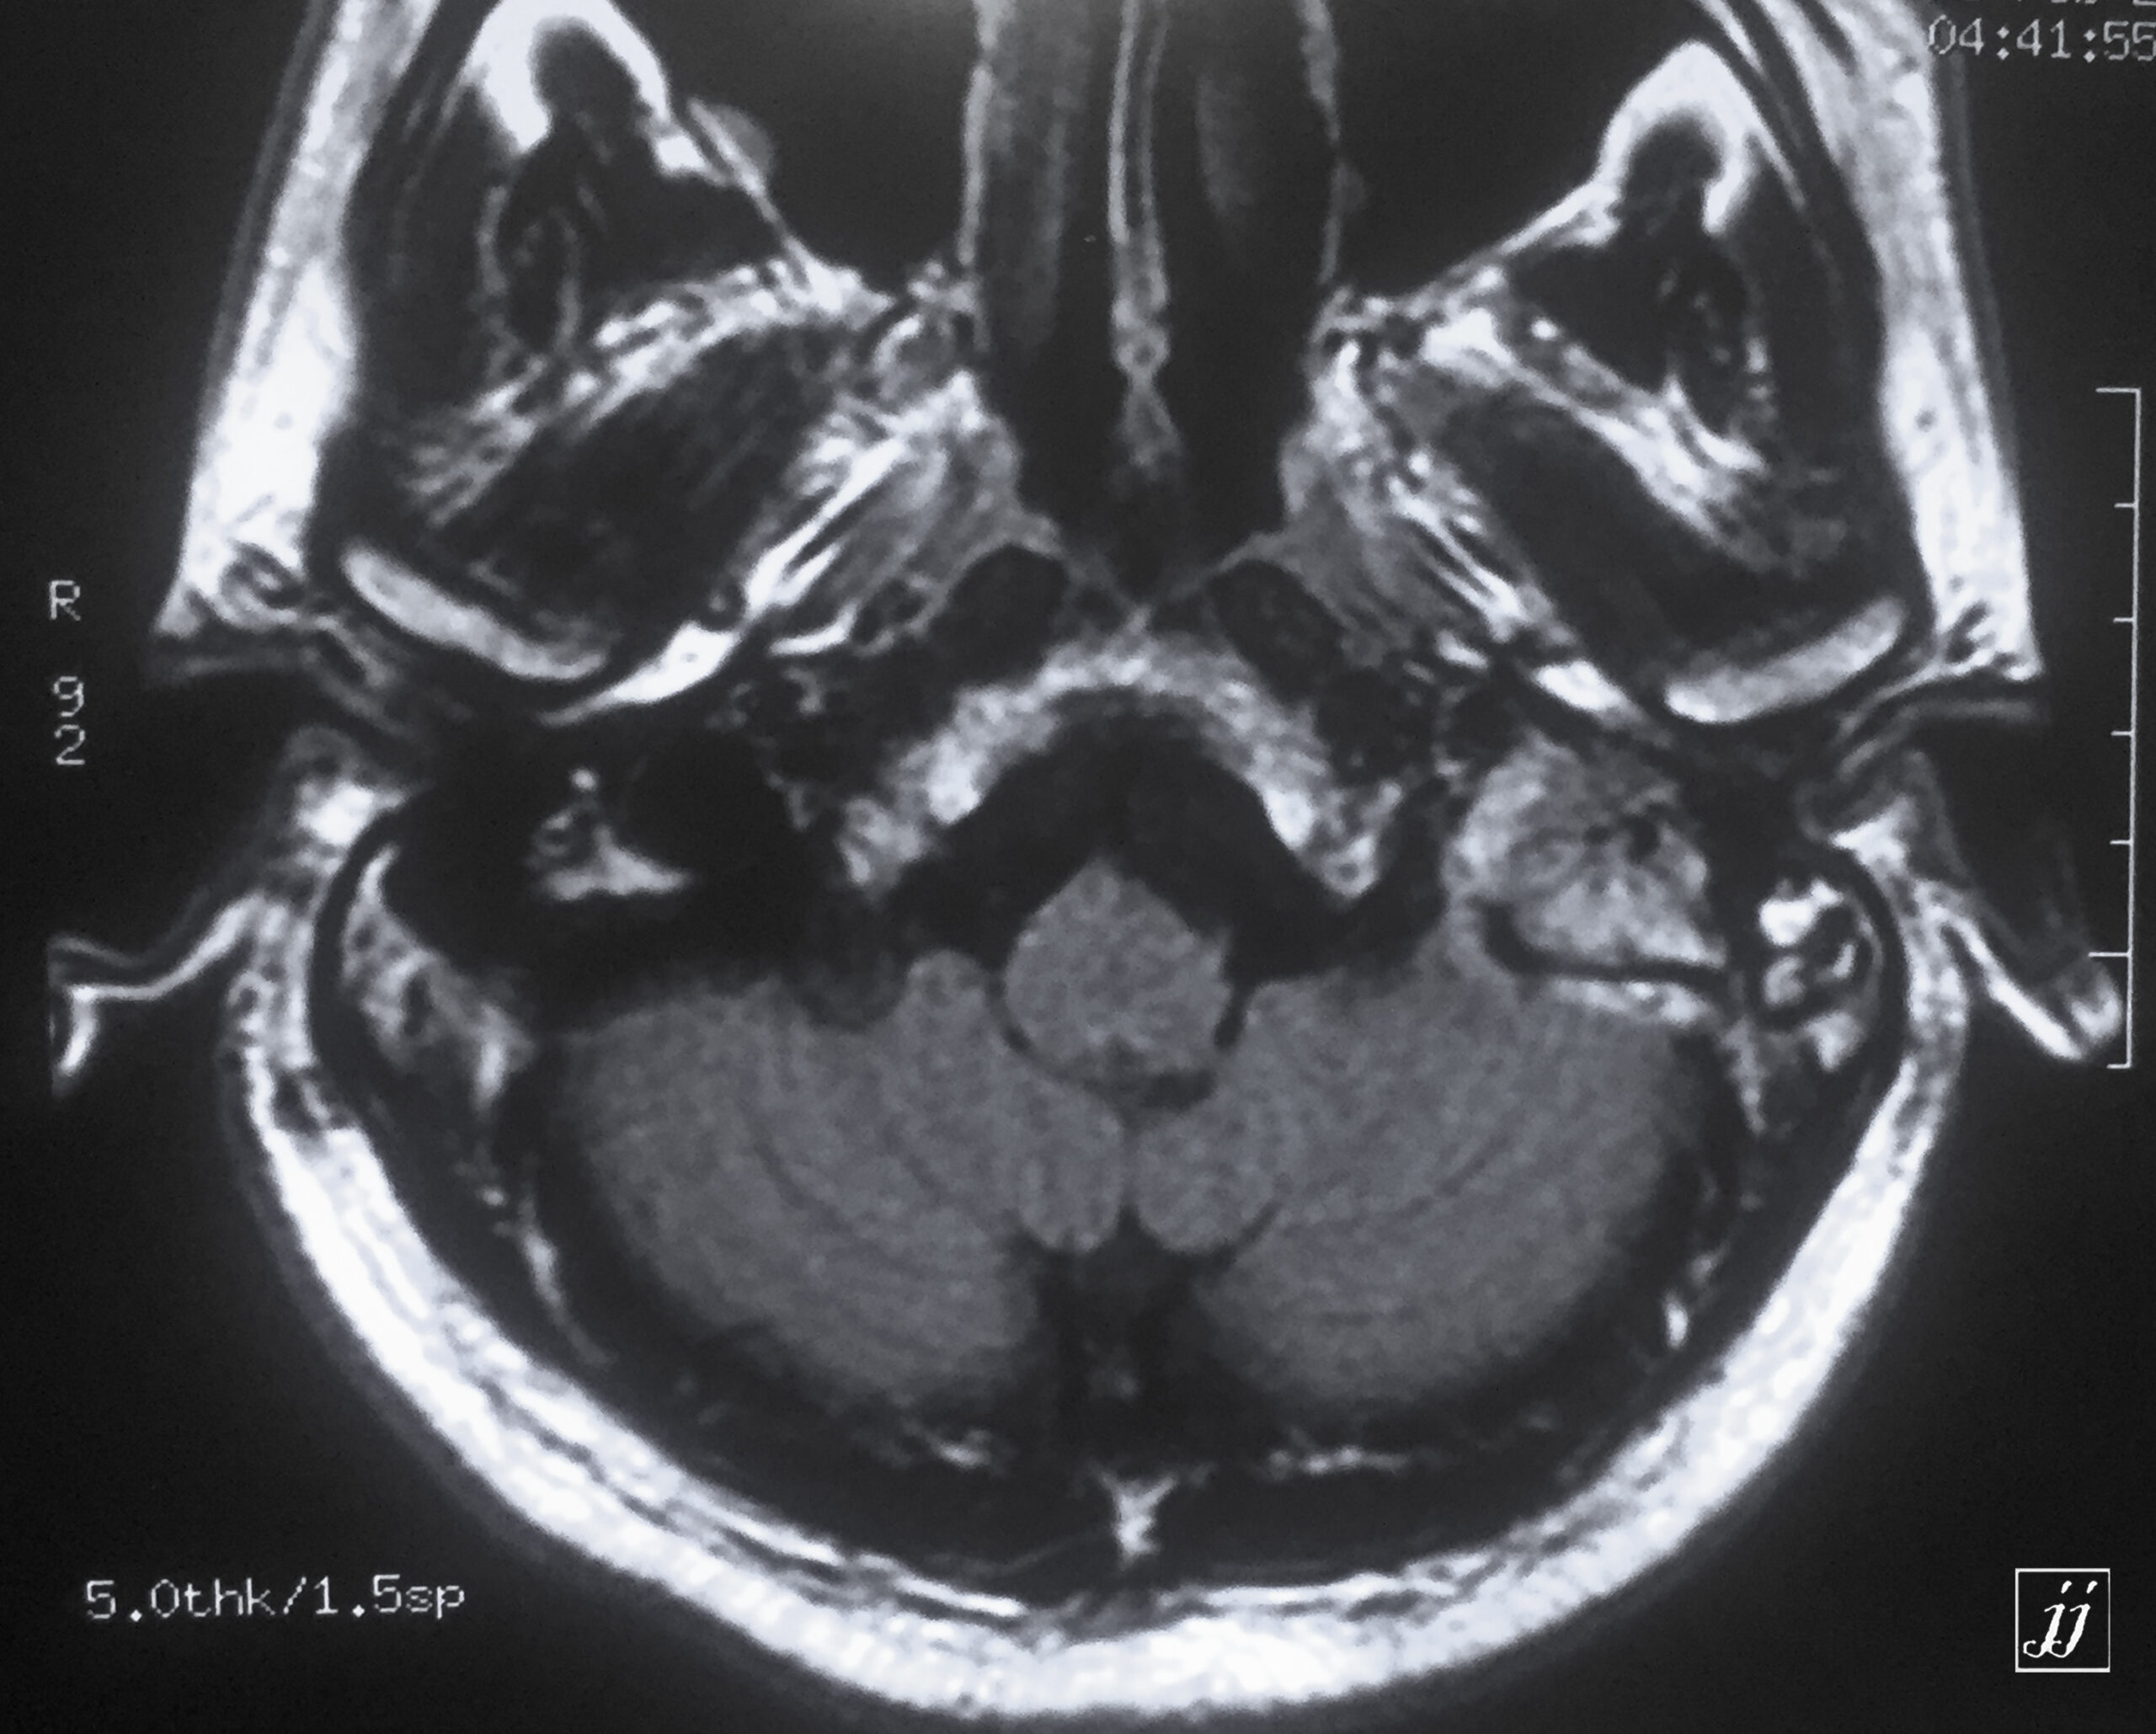

Brain- left glomus jugulars tumor (4)